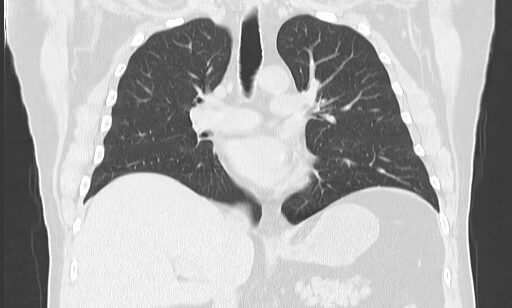

Computed tomography angiography (CTA) combines a CT scan with a special dye or contrast material to produce pictures of blood vessels and tissues in a section of your body.

CT angiography uses a CT scanner to produce detailed images of blood vessels and tissues throughout the body. An iodine-rich contrast material (dye) is usually injected through a small catheter placed in a vein of the arm. A CT scan is then performed while the contrast flows through the blood vessels to the various organs of the body. After scanning, the images will be processed using specialized software and a computer, and reviewed in different planes and projections.